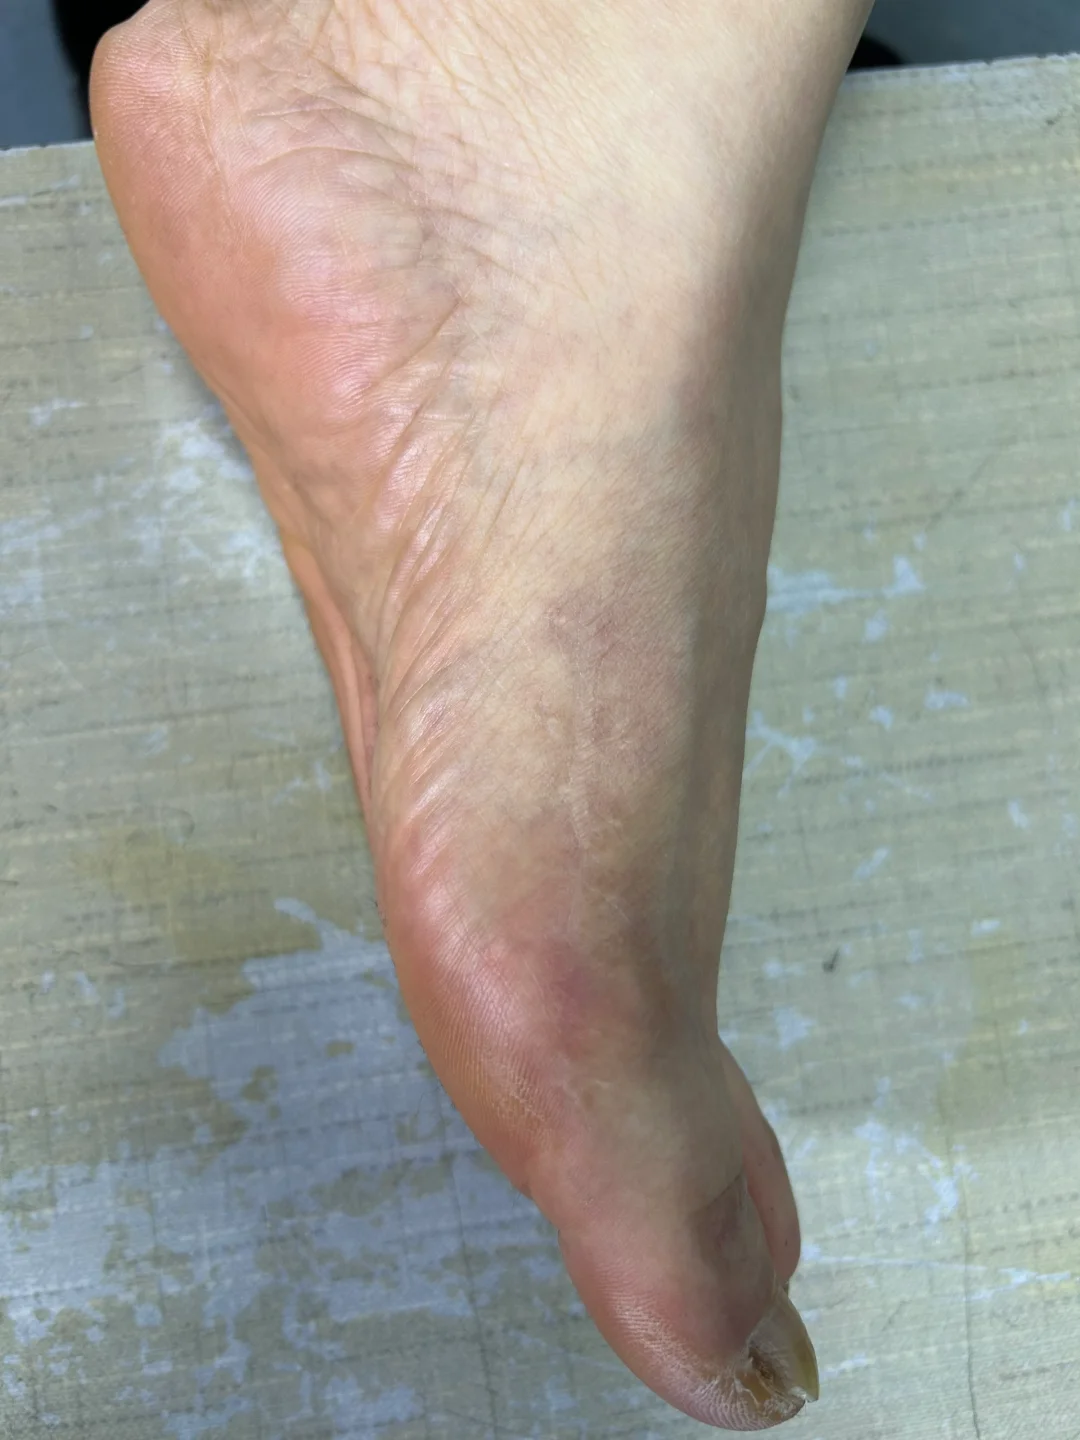

拇外翻术后三年半

手术伤口瘢痕变成白色,术后半年隆起,一年内色深,等2年后慢慢变白。 即使当初缝合愈合并没有那么好,当初没有全部内缝,还有部分外缝的蜈蚣瘢 关节稳定,匹配良好,无不适,没有复发可能 片子上缺损的三角骨区域长满新骨,骨痂下成骨不需要担心。 新骨密度高,都是气质骨,所以强度远高于术前